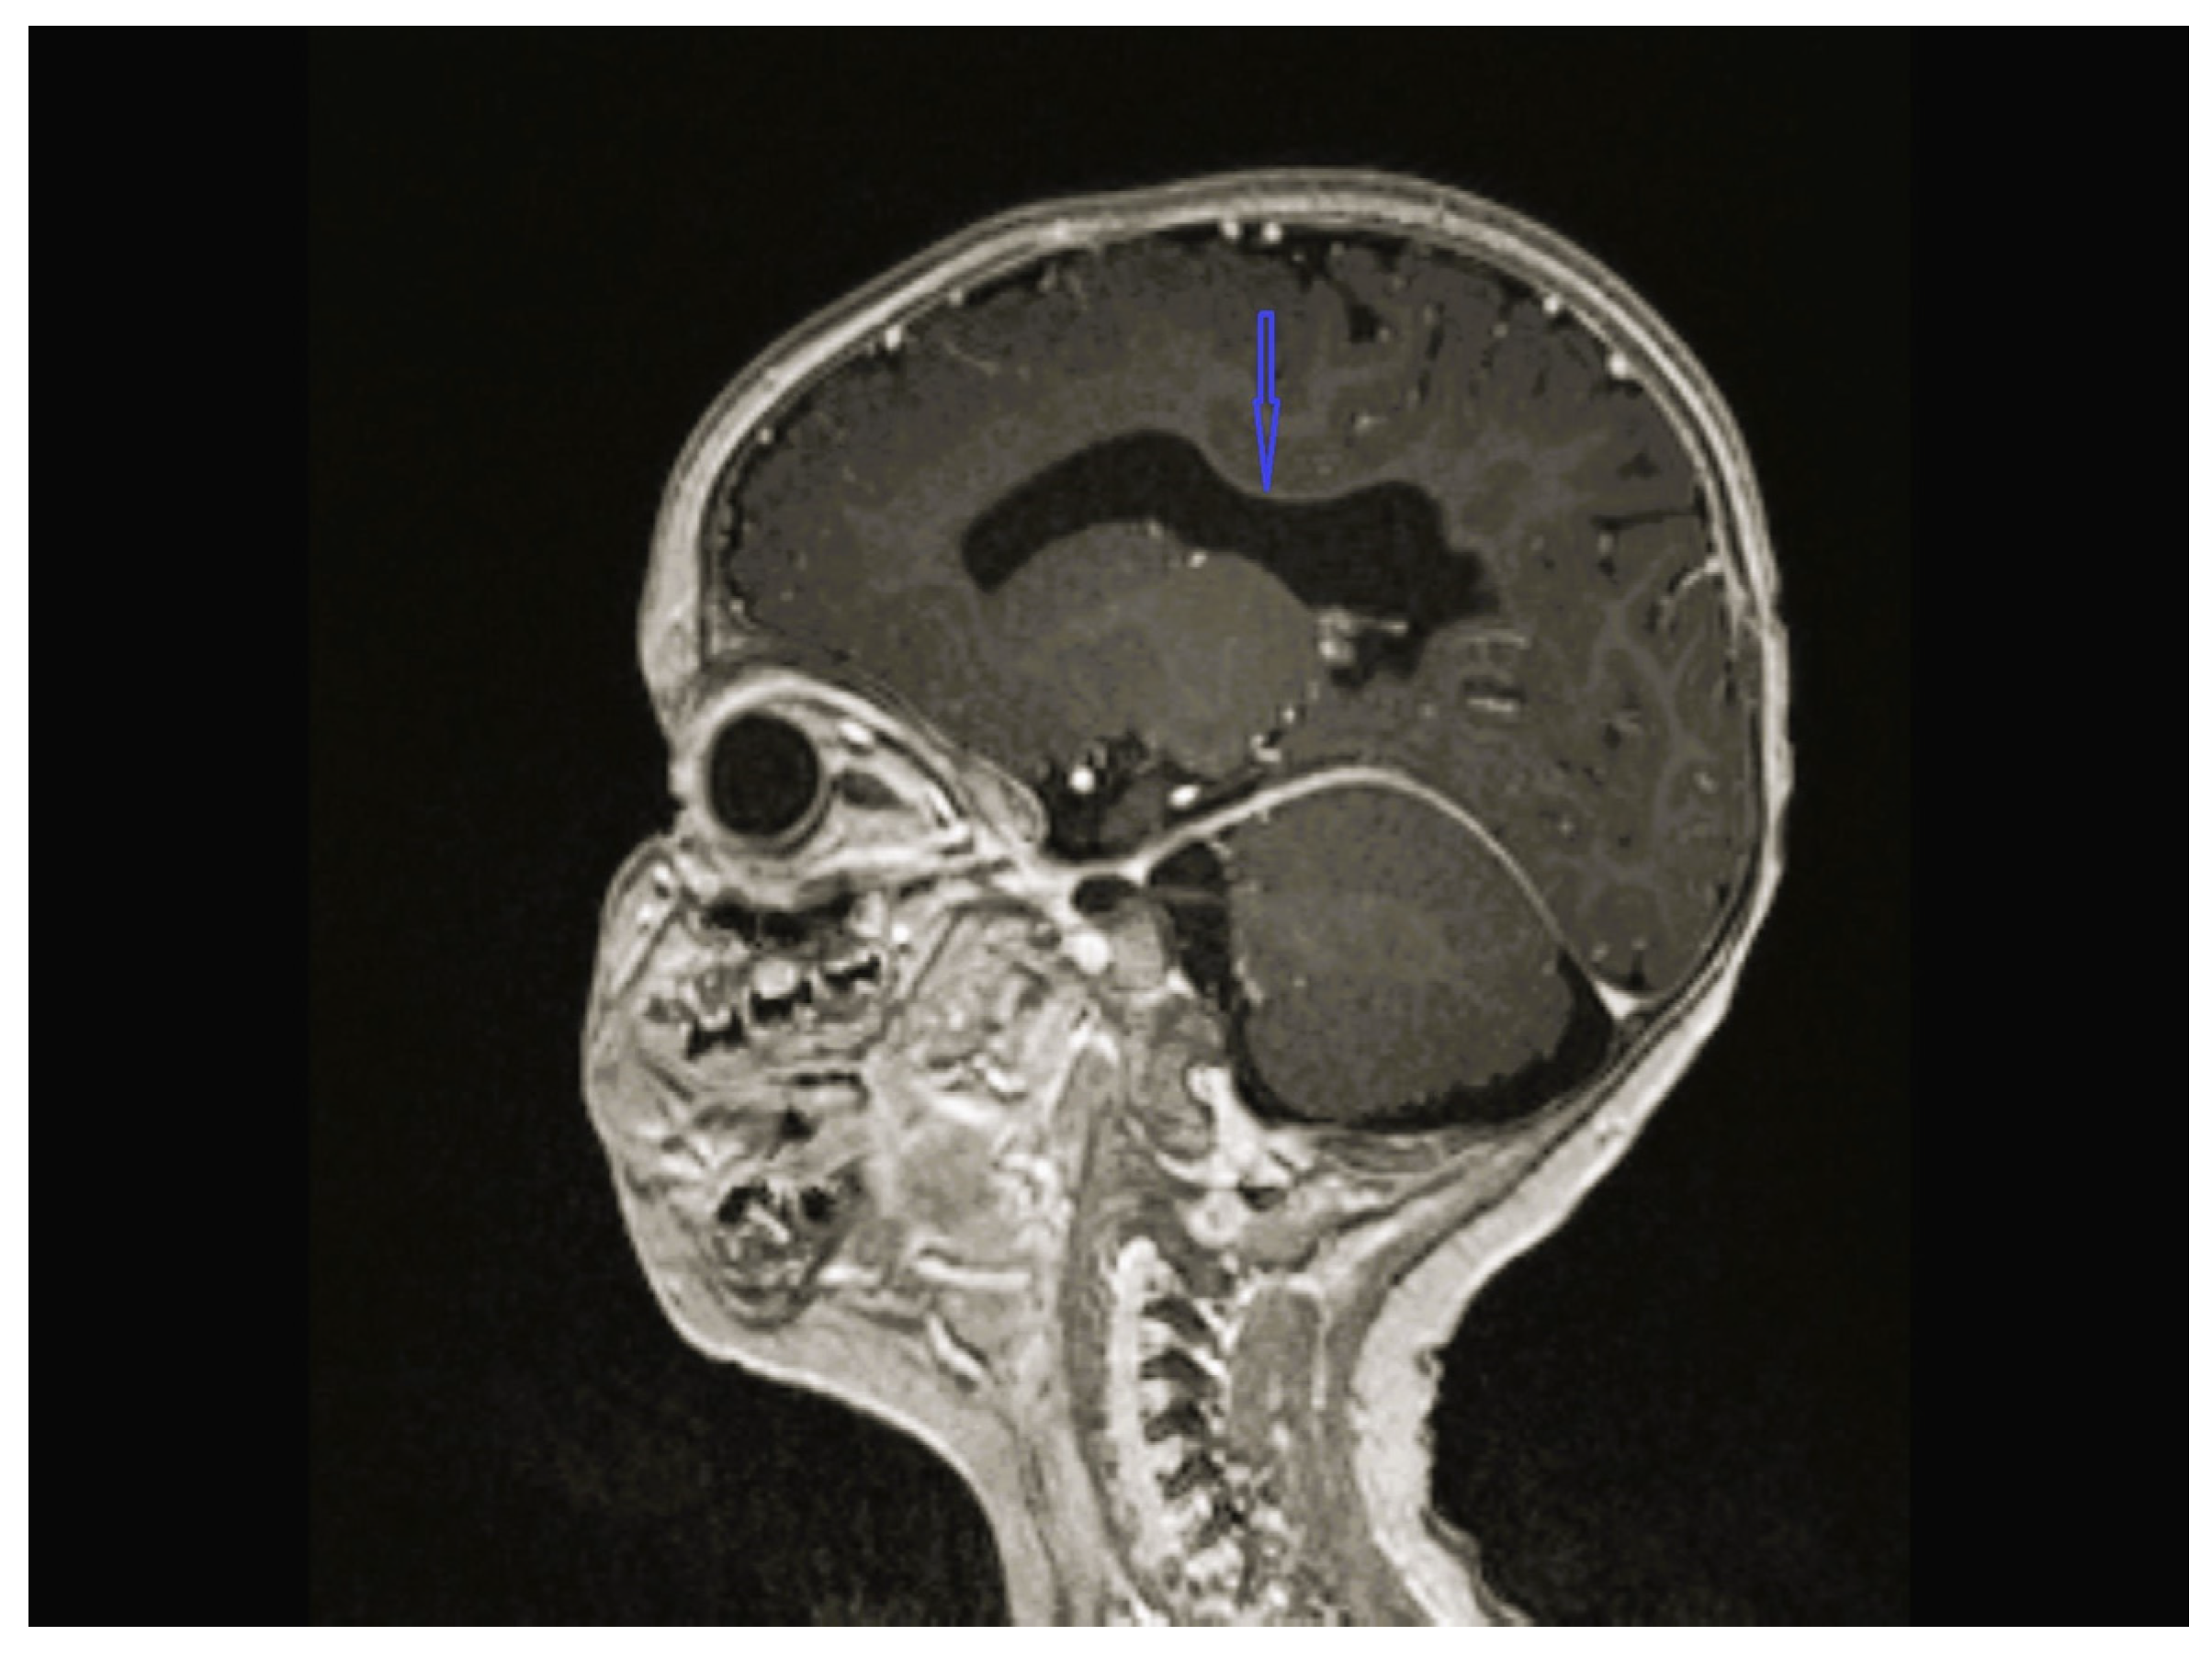

| 2 | Normal | Normal | Centrotemporal spike and waves on the left side with normal background | CC hypoplasia | Normal | GBA2 NM_020944.3 c.1688-2A>C heterozygote | Physical therapy, baclofen, diazepam, orthopedic braces, levetiracetam |

| 8 | Normal | - | Multifocal spike and waves pattern | Vermian, CC and brainstem hypoplasia | Normal | KIDINS220 NM_020738.4 c.4388C>A heterozygote p.S1463* | Physical therapy, clonazepam, sodium valproate |